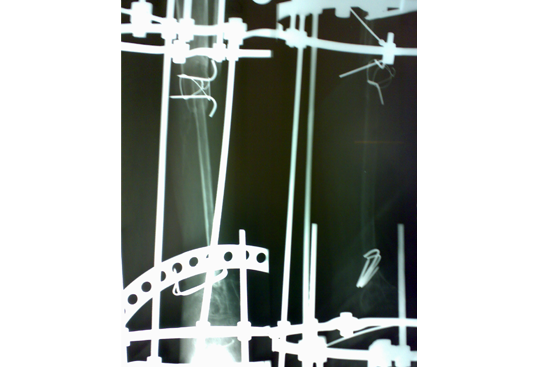

We have done Huntington technique by stage ilizarov procedure. Here is the diagrammatic representation of our method.